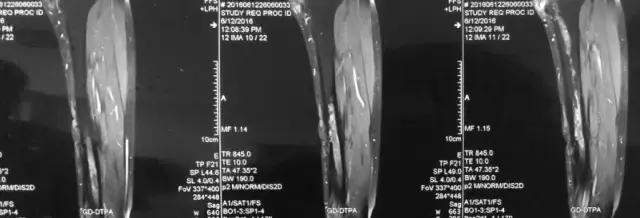

影像检查

诊断:感染。 检查:膝关节MRI,确认伤口窦道是否与髓腔相通。 治疗:1、血沉和C反应蛋白正常,目前无需特殊处理。 2、如果窦道反复出现或血沉和C反应蛋白升高可考虑手术。如证明窦道与髓腔相通,需行扩髓。

1、诊断:感染。(如果窦口与髓腔相通就是骨感染) 2、检查中血沉和要动态检查。如果局部红肿伴胀痛就查。 3、如果扩髓需要远近端开口。

核磁示中下段骨髓炎,上面切口处流脓,请问张主任你的意见要上手术吗?